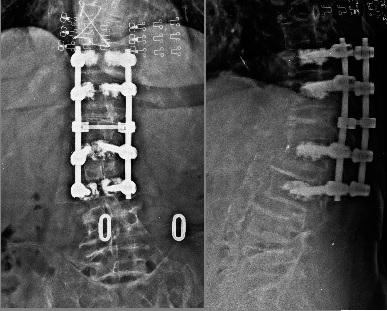

Direkt grafi

Resim 4: Direkt grafide L4 vertebrasına bir, L5 ve S1 seviyelerine ikişer vida konularak bu sistemin eski rod sistemine dominolarla bağlandığı görülüyor. L5 vidaları inferiordan gitmektedir (malpozisyon). S1 vidalarında biri lateral grafide görülememektedir. L5 ve S1 korpuslarında sement mevcuttur.